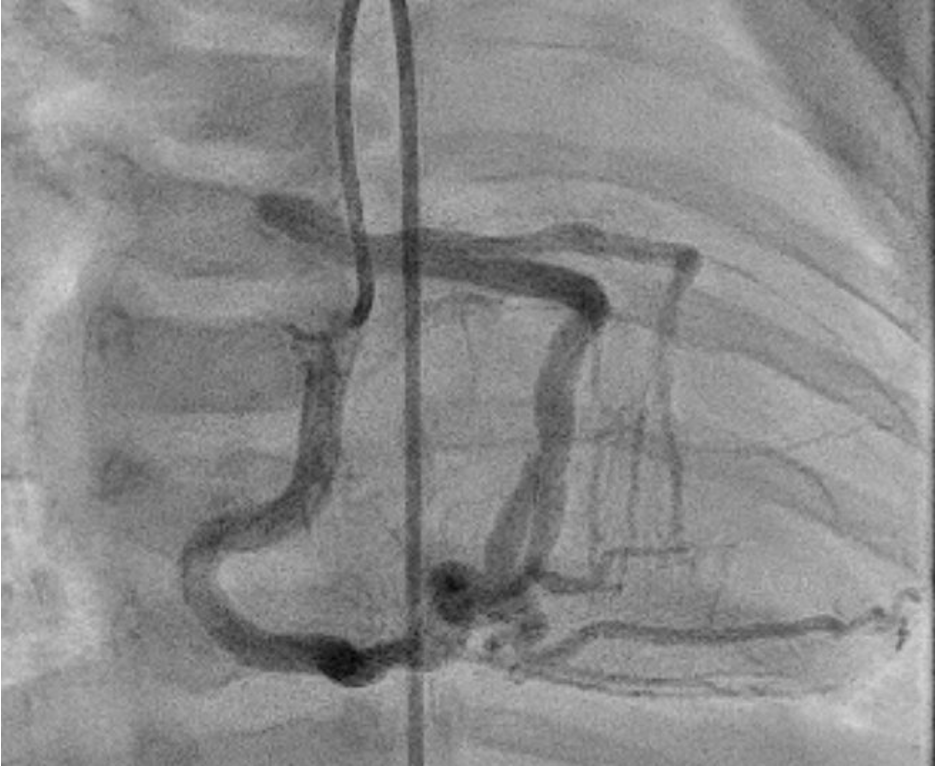

Has anyone seen this coronary pattern before? #ALCAPA from RPA. Large collaterals of RCA to LCA that supplies the left system. Stenotic origin of LCA at PA. #CHD #pedscards #cardiotwitter #radialfirst @NCProvider @UofLPeds @UofLPedsCCM @JFurlongDillard @deanna_md